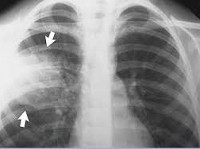

Рентгенологическое исследование (рентгенография легких в двух проекциях) позволяет визуализировать пневмоническую инфильтрацию легочной ткани (в виде интенсивного затемнения доли или очаговой тени), определить наличие плеврального выпота. С целью дифференциальной диагностики с раком легкого, туберкулезом, ателектазом применяется линейная и компьютерная томография (КТ легких).